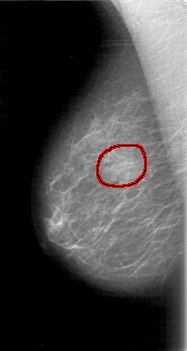

FILE: D_4015_1.RIGHT_CC.OVERLAY

TOTAL_ABNORMALITIES 1

ABNORMALITY 1

LESION_TYPE MASS SHAPE OVAL MARGINS OBSCURED

ASSESSMENT 0

SUBTLETY 4

PATHOLOGY BENIGN

TOTAL_OUTLINES 1

BOUNDARY